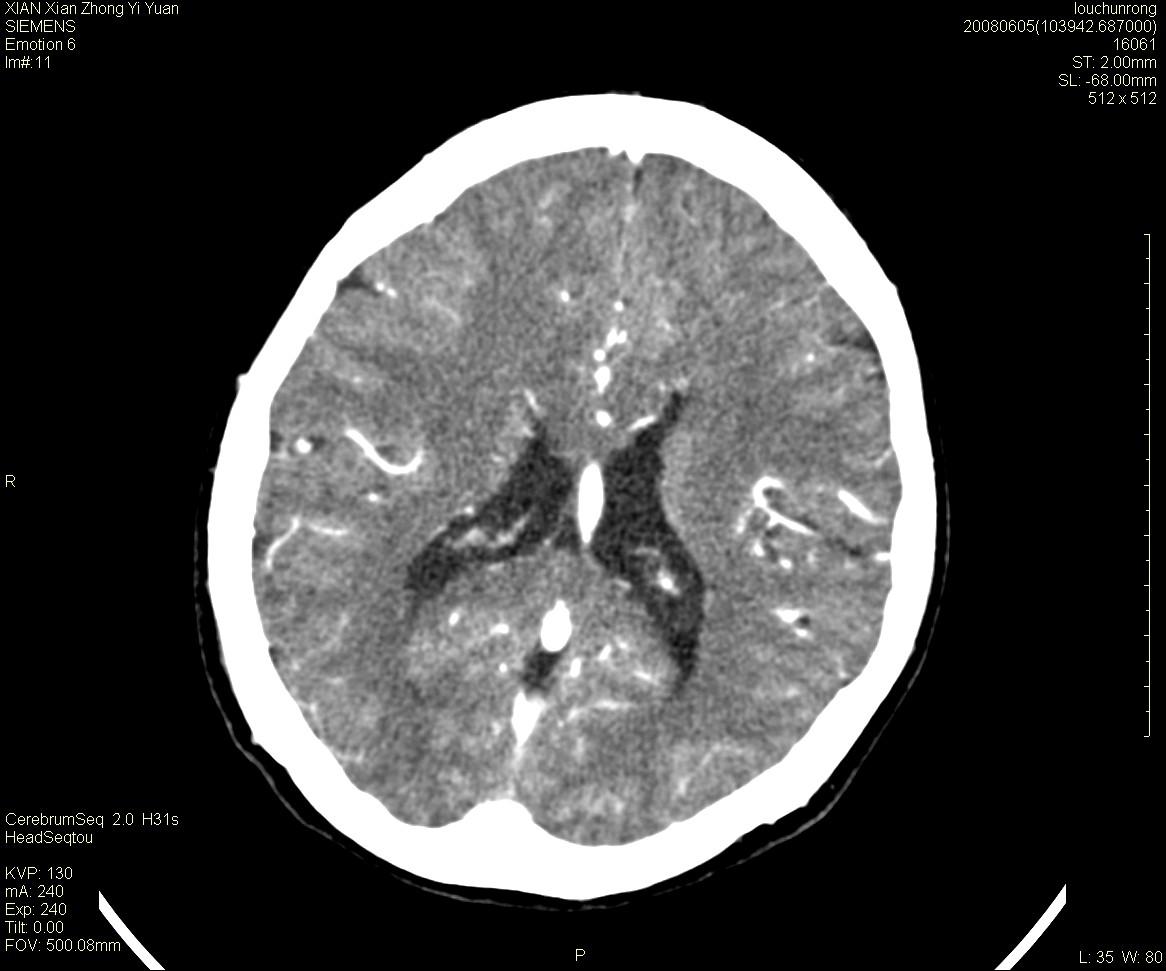

标题: CT13860:F52Y,,头外伤致头晕半天,以前无不适。 [打印本页]

标题: CT13860:F52Y,,头外伤致头晕半天,以前无不适。

层厚2mm。

左侧侧室内血管异常增粗,考虑血管变异或血管瘤可能,余未见异常

大家看左额叶大脑镰旁高密度影

两侧脑室体部距离增宽,胼胝体发育不良?

中线附近、枕叶近枕骨处及脑内多发点条状强化影,考虑血管异常?

大脑大静脉池内的密度不均,双侧脑室增宽,我看右异常这块。战友们看看

侧脑室前角变形、变窄,考虑侧脑室粘合;余未见明显异常。